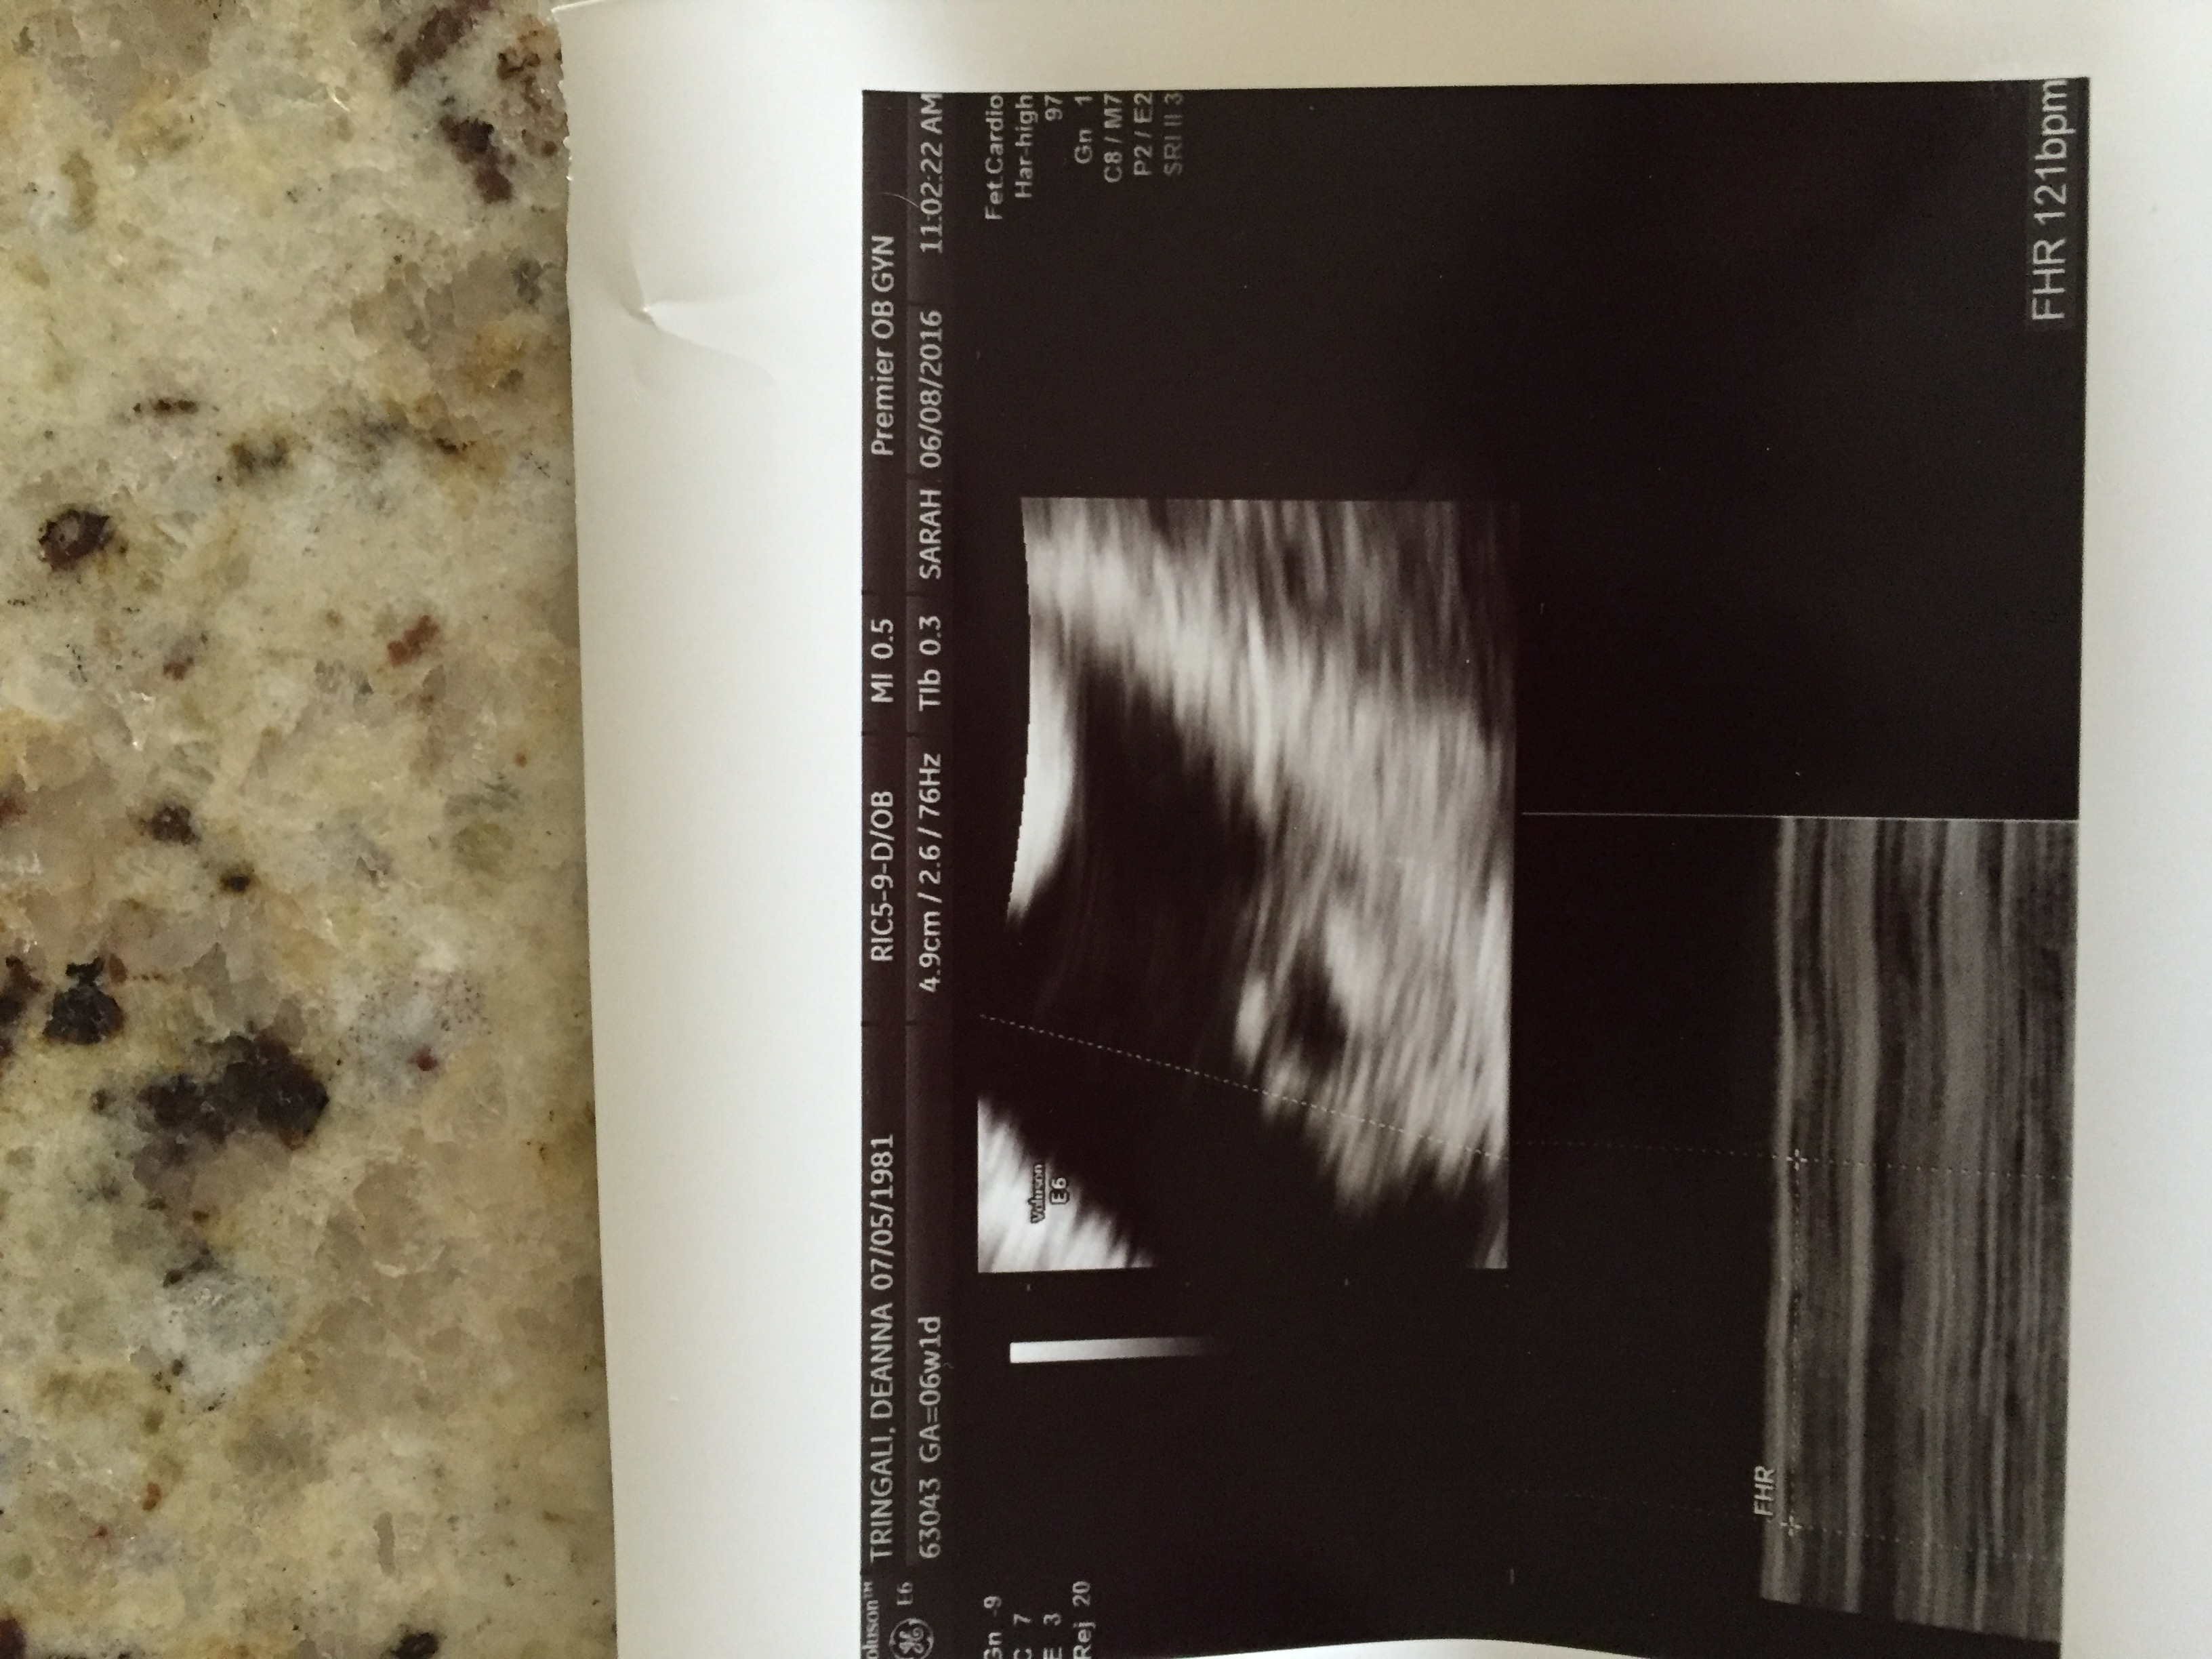

Ramzi 5.5 week ultrasound

Attachment 31657

Transvaginal ultrasound...